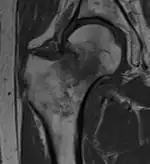

X-ray showing a suspected compressive subcapital fracture as a radiodense line -

CT scan shows the same, atypical for a fracture since the cortex is coherent -

T1-weighted turbo spin echo MRI confirms a fracture, as the surrounding bone marrow has low signal from edema.